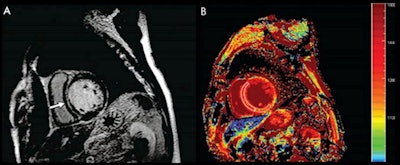

Imaging in a 60-year-old man with dilated cardiomyopathy and septal fibrosis. (A) Late gadolinium enhancement was found in the mid-wall of the interventricular septum (arrow). (B) Noncontrast-enhanced T1 mapping shows that the native T1 value of the septal region including late gadolinium enhancement (enclosed by a white line) is 1,382.2 msec, which is more than 1,349.4 msec ± 1.2 (standard deviation) above that of the minimum T1 value (enclosed by a green line, 1262.4 msec ± 62.0) in this patient. Images and caption courtesy of the RSNA.Cardiac MRI could be a powerful heart disease screening tool, but its cost and its place in the radiology department workflow needs more investigation, the group wrote.